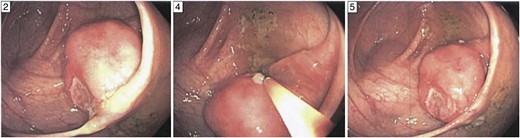

The patient presented to the emergency department 5h post-procedure complaining of abdominal pain and had a firm abdomen. He had a leukocytosis of 17 000. His Computerized Tomography (CT) scan showed a significant amount of pneumoperitoneum and inflammatory changes in the right lower quadrant in the region of the terminal ileum and cecum (Fig. 2). As the patient was improving, we initially attempted a trial of non-operative management. In the interim, pathology from the endoscopic biopsy had returned as extramedullary plasmacytoma. A baseline carcinoembryonic antigen level was 0.8. After ∼48 h the patient manifested signs of unsuccessful non-operative management characterized by increasing abdominal pain, tachycardia and rising leukocytosis. Therefore, we decided to perform an exploratory laparotomy.

Colonoscopic perforation on CT. CT scan of the abdomen revealing significant intra-abdominal free air (left). On a lower portion of the scan, there are inflammatory changes evident in the right lower quadrant in the region of the ileum and cecum (right). These structures are difficult to discern in the presence of the inflammatory changes.